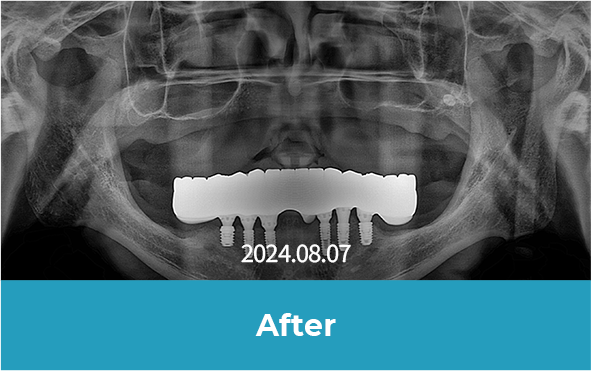

치료 후 사진

[ 환자분의 동의서 작성 후 게시하였습니다 ]